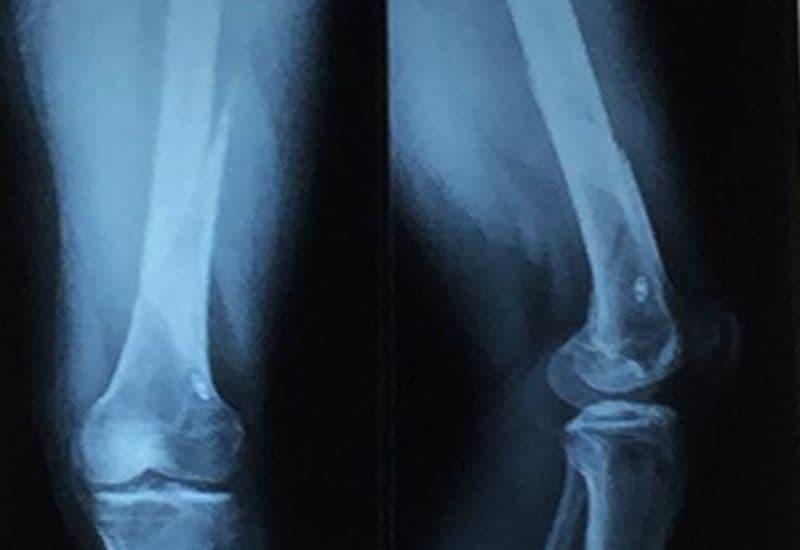

Bác sĩ sẽ chẩn đoán trật khớp gối dựa trên các triệu chứng lâm sàng và cận lâm sàng như chụp X-quang hoặc chụp cộng hưởng từ (MRI). Trong đó, chụp X quang thường giúp bác sĩ xác định được vị trí xương bị trật. Còn chụp MRI giúp cung cấp hình ảnh một cách chi tiết hơn về các mô mềm, dây chằng và sụn khớp.

Chụp X quang có thể giúp nhận diện trật khớp gối, đây là tình trạng cấp cứu y khoa cần được điều trị nắn trật càng sớm càng tốt.